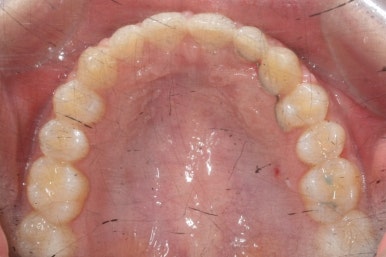

위 사진들은 부산매복치아교정 키다리아저씨치과에 처음 내원하셨을 때의 모습입니다.

화살표 표시한 부분이 바로 영구치 송곳니가 있어야 할 자리인데, 매복이 되어있고 대신 유치가 여전히 남아있는 모습입니다.

환자분의 나이가 만으로 15세였는데, 치과에 처음 올 때 해당 치아가 영구치가 그냥 썩은 줄 알고 오시는 경우가 많습니다.

마무리 때의 사진입니다.

윗니만 부분교정하였지만 교합에도 이상 없이 매복되었던 송곳니는 매우 잘 위치를 잡았습니다.

부산매복치아교정 상악 부분교정을 통해 매복치를 교정해준 이번 치료의 전후사진 비교입니다.

썩은 유치 대신 영구치 송곳니는 매우 자연스럽게 위치되었습니다. 아랫니는 교정하지 않았기 때문에 약간 삐뚠 느낌은 남아있지만 맞물림은 크게 문제가 없게 마무리 되었습니다.